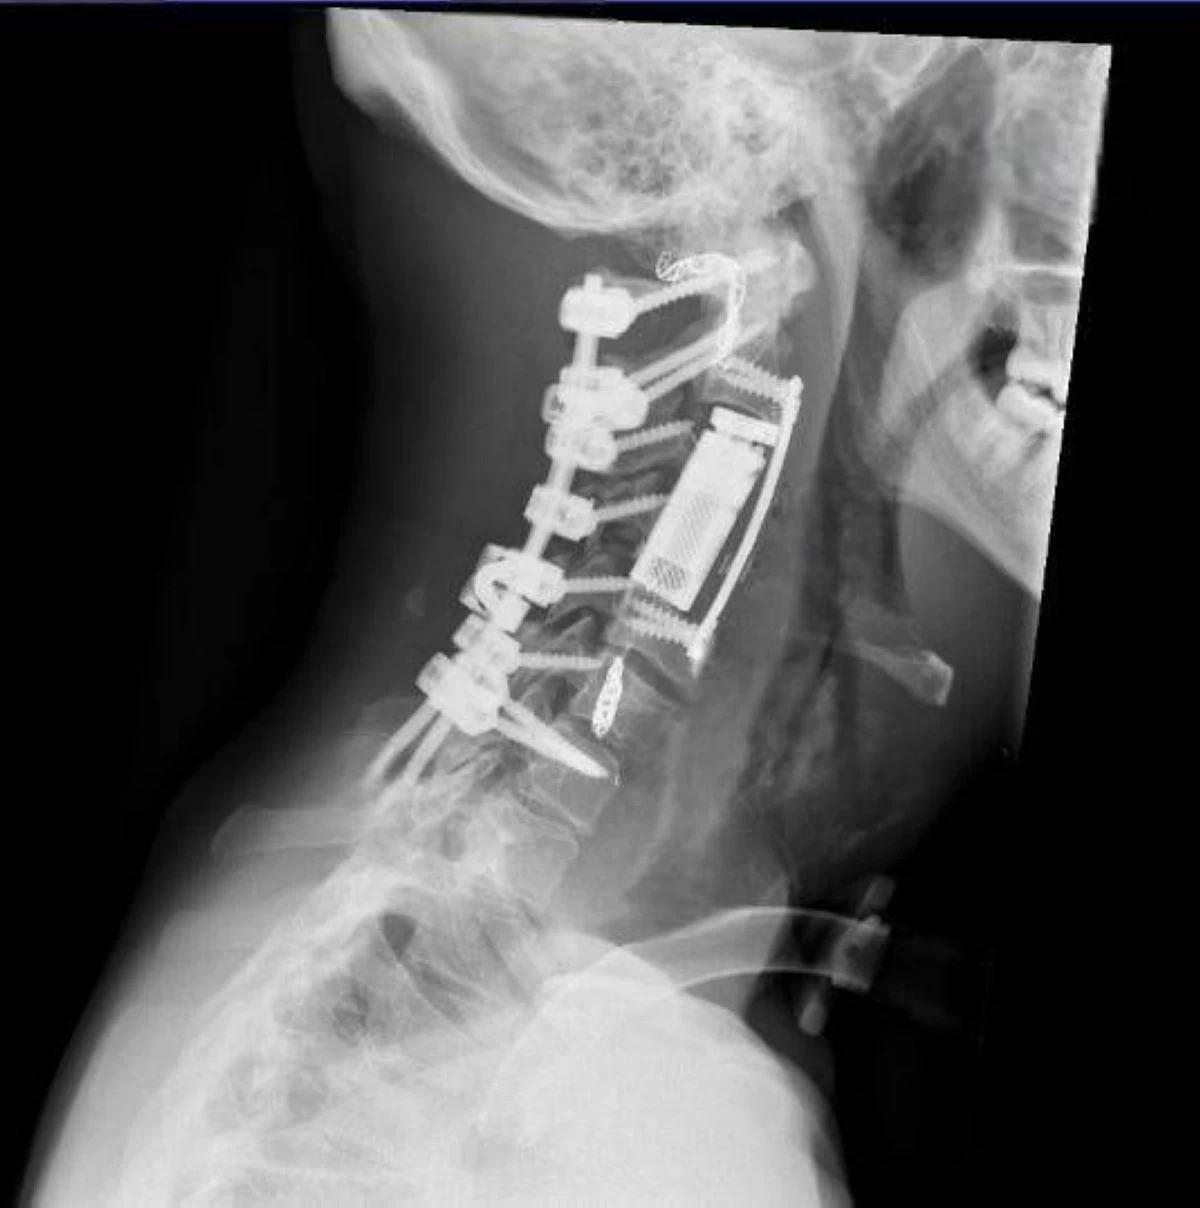

وتابع بأنه في المرحلة الجراحية تم تثبيت العمود الفقري من الفقرة الأولى إلى السابعة عبر عملية خلفية دقيقة، واستئصال الورم بالكامل بطريقة En Bloc، أي كتلة واحدة من الجهة الأمامية للعنق، كما تم تعويض الفقرات المزالة باستخدام قفص فقري تمددي (Expandable Cortectomy Cage)، مع تثبيت أمامي لضمان الاستقرار الكامل.

وأشار الفريق إلى أن هذه العملية لا ترى إلا في مراكز عالمية متقدمة، نظرا لتشريح الورم الدقيق، حيث تم استئصال أكثر من فقرة وشريان رئيسي محيط.